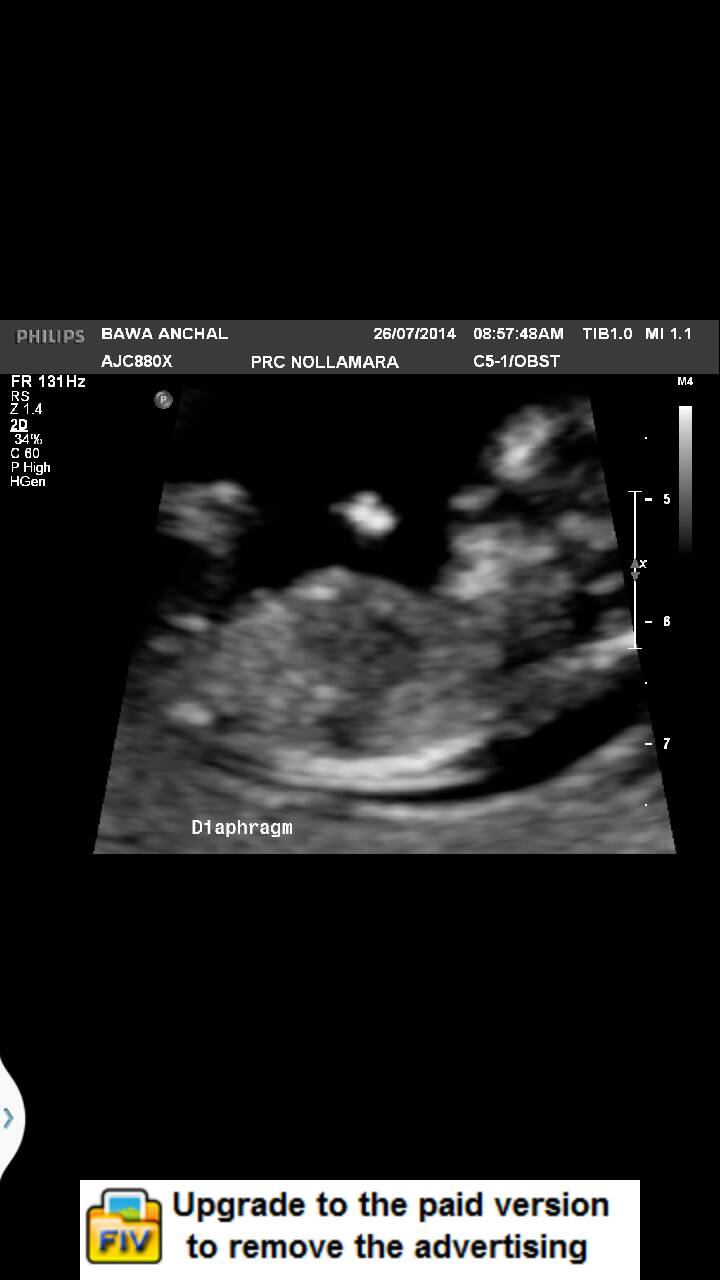

I had my 12 week scan yesterday, I am so exvuted to know what am I carrying. Cab you pkesse ma ke guesses from yh e lovrly images?Attachment 20022Attachment 20022Attachment 20023